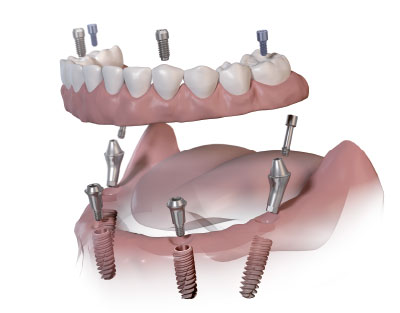

L’objectif de la mise en charge immédiate est de fournir au patient une restauration rapide de la fonction qui peut être masticatrice mais aussi esthétique dans les 0 à 72 heures après la pose

Cette technique requiert avant tout une bonne stabilité primaire des implants puis une contention à la fois fixe, rigide et passive des implants entre eux grâce à une prothèse transitoire qui jouera le rôle de fixateur externe.

Pour les cas à visée esthétique, cette prothèse transitoire peut avoir également un rôle pour le guidage des tissus mous. La mise en charge immédiate est un protocole qui permet de diminuer la durée du traitement et d’éviter au patient le passage par des solutions prothétiques provisoires inconfortables du fait de leur mobilité, sans pour autant compromettre le taux de survie implantaire.